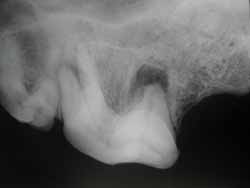

(JPG)

infezione periapicale

La polpa dentale necrotica esita in infezioni nell’osso che accoglie il dente colpito, queste infezioni si manifestano radiograficamente e vengono indicate come reazioni periapicali.